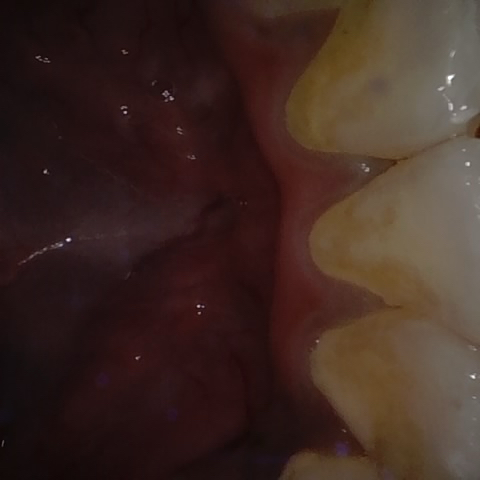

Annotated as "Good"